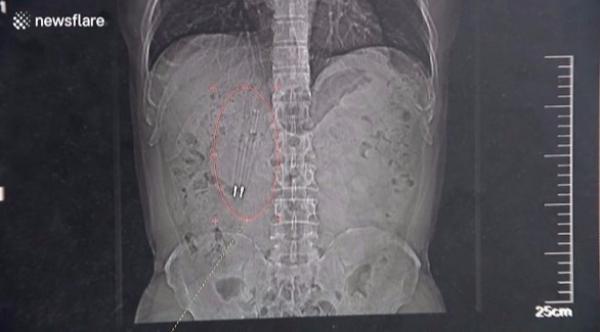

قام الجراحون في أحد المستشفيات الصينية بإخراج قلمين من معدة رجل صيني يدعى وانغ، بعد أن بقيا في جوفة لمدة 36 عاماً.

وقال الجراحون في مستشفى سوتشو، بمقاطعة جيانغسو الصينية، بأن الرجل قال لهم إنه ابتلع القلمين قبل 36 عاماً بعد خسارته لرهان مع أصدقائه.

وقال وانغ للأطباء بأنه نسي ابتلاعه للأقلام طوال تلك الفترة حتى فبراير (شباط) الماضي، عندما أجرى صوراً شعاعية لجسمه.

من الجدير بالذكر بأن الأطباء نجحوا باستخراج الأقلام من جوف وانغ في الرابع والعشرين من أبريل (نيسان) الماضي، وهو يتمتع الآن بصحة جيدة، بحسب موقع "يو بي آي" الإلكتروني.